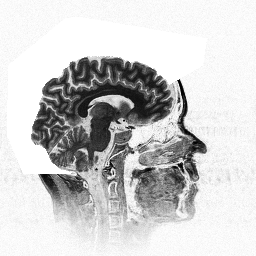

Na slici 1. prikazan je poprecni presjek glave covjeka, dobiven pomocu MR. Ova metoda pogodna je za uzorkovanje jer zracenje nije opasno, no na snimcima zbog fizikalnih razloga nije moguce izdvojiti kostano tkivo, koje je inace vrlo dobro uocljivo na CT snimcima. Na poprecnom presjeku mozemo uociti opcrtan poligon, oko mozga pacjenta, sto je ucinjeno na svim poprecnim presjecima. Izdvajanje poligona ostvareno interaktivnim metodama obrade slike, omogucava vidljivost mozga na konacnom trodimenzionalnom liku.

Slika1.Poprecni presjek glave.

Ulazni podaci opisani u prethodnom poglavlju mogu se vizualizirati na razne nacine, no za podatke dobivene u medicini [1], [9] ili strojarsvu najpogodniji je prikaz pomocu metode pokretne kocke [6], [7], [10]. Naime, za ovakove podatke obicno postoji ostra granica izmedju tkiva koje treba prikazati i okoline. Na slici 3 prikazan je rezultat koji se postize povezivanjem poprecnih presjeka u trodimenzionalnom prostoru. Za objekt na slici 3, upotrebljeno je 100 poprecnih presjeka razlucivosti 256x256x8, od kojih je pedeseti prikazan na slici 1. Objekt na slici 4 rezultat je upotrebe istih ulaznih podataka uz vecu vrijednost praga.

Slika 3. Na osnovi poprecnih presjeka dovbivenih pomocu MR, nacinjen je trodimenzionalni objekt.